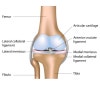

무릎 관절의 해부학